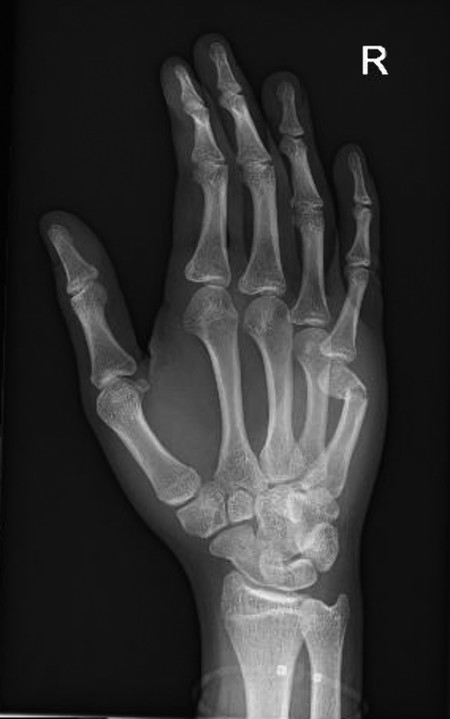

14.5 Fracture Dislocations of the Base of the Fourth and Fifth Metacarpals

These injuries can be easily missed and that is why it is essential to always examine three views (anteroposterior [AP], lateral, oblique) in the emergency department (Fig. 14‑10 a,b). They are inherently unstable and even after reduction under anesthesia the base of the fourth and fifth metacarpal will often re-dislocate even in a well-molded plaster cast.